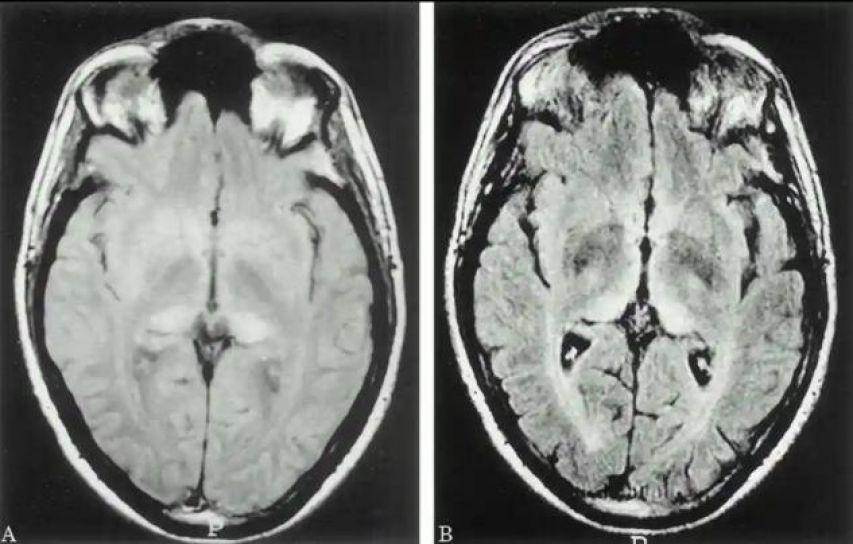

【正常人腦(左)和患病人腦的對比】

感染朊病毒後,動物的神經系統會受到朊病毒的攻擊,腦組織也會因此產生嚴重的損害

因爲朊病毒會誘導正常的朊蛋白髮生構象變化,從而形成更多的朊病毒。

這些異常蛋白在神經細胞內聚集,破壞神經細胞的正常結構和功能,最後導致神經系統的紊亂和崩潰。